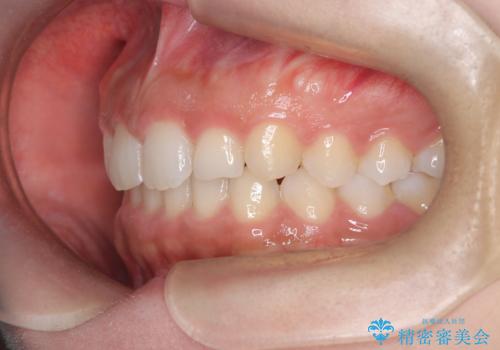

- 患者様は、ディープバイト(深い噛み合わせ)と、咬合平面の左下がりが気になるとのことでご来院されました。診断の結果、非抜歯で治療可能と判断し、透明なマウスピース型矯正装置「インビザライン」を用いる方針としました。治療では、歯列全体の調整を行いながら、咬合平面の水平化を重点的に進める計画を立案しました。2年間で計画的にマウスピースを交換し、左右のバランスと噛み合わせの改善を目指しました。

ディープバイトの矯正は、噛み合わせが深くなりがちなため、細心の注意を払いながら進める必要があります。本症例では、奥歯の高さを調整しつつ前歯の噛み合わせを浅くすることで、全体の咬合バランスを整えました。また、咬合平面の左下がりを修正する過程で、歯列に不均等な力がかからないよう、インビザラインのアタッチメント配置を最適化しました。患者様には装着時間を守っていただき、治療が計画通り進むよう協力をお願いしました。治療終了後には、リテーナーを装着して安定性を確保しました。